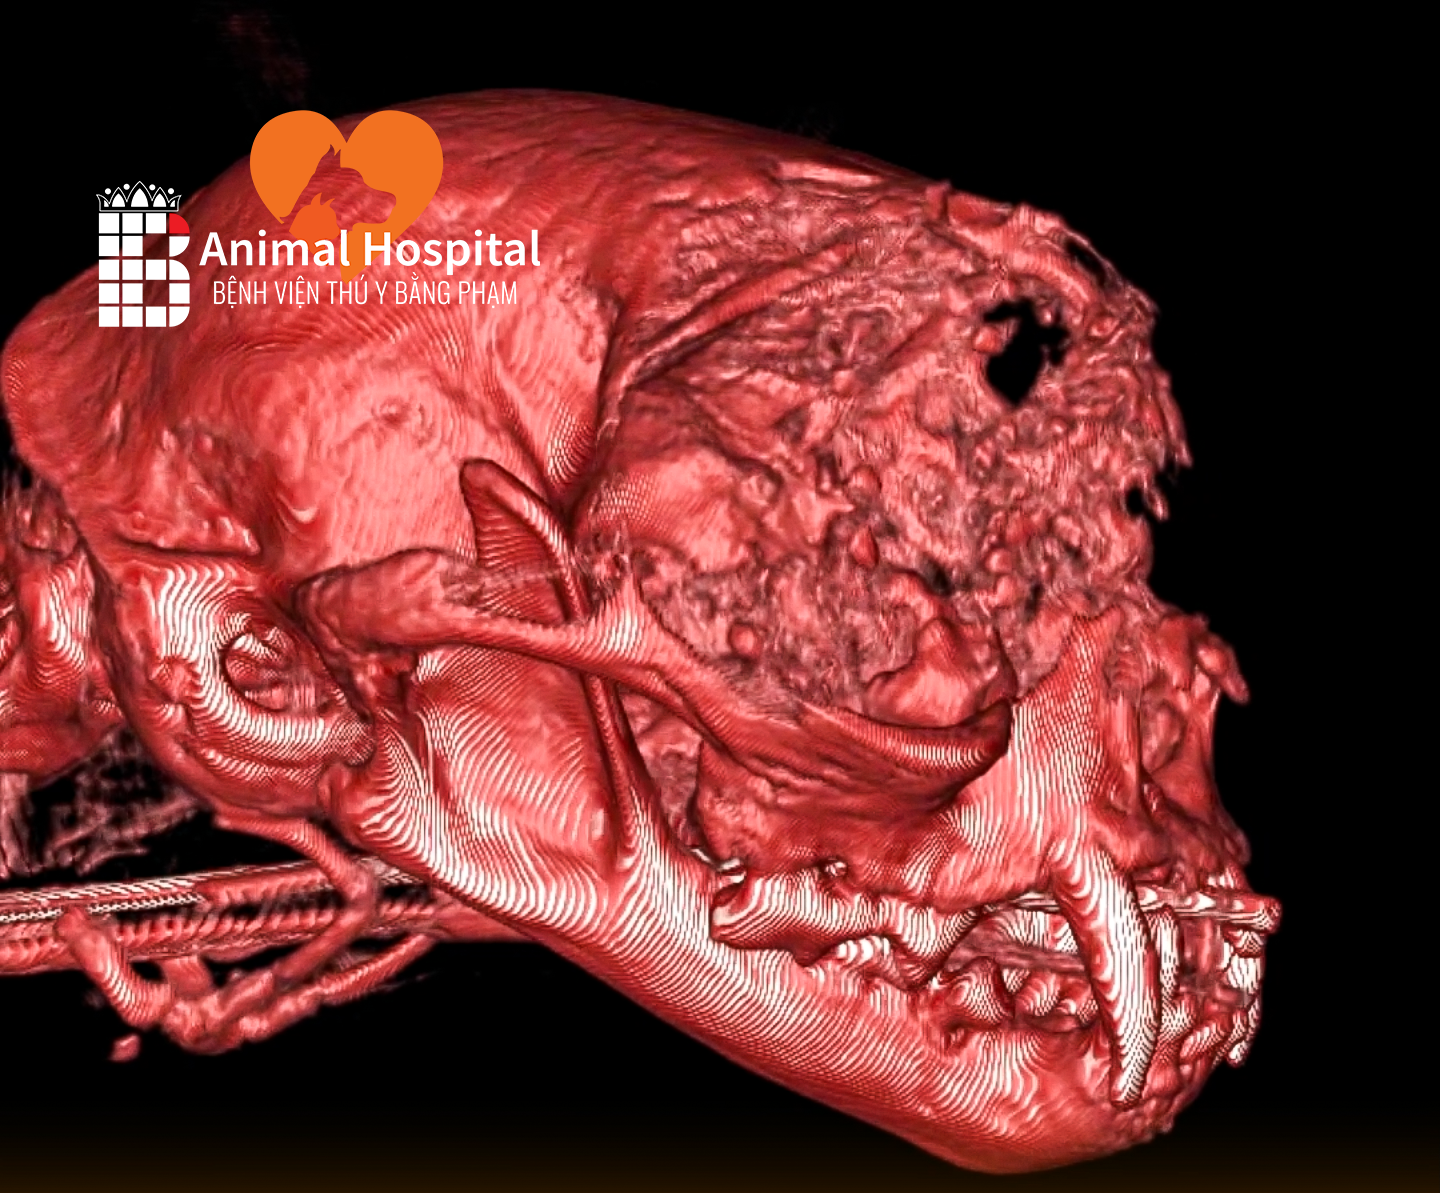

- Chụp X-quang (X-ray) để xác định chính xác vị trí và loại gãy xương (type of fracture).

- Nhấn mạnh: Phẫu thuật chỉnh hình xương (orthopedic surgery) đòi hỏi trang thiết bị chuyên biệt (thiết bị cố định bên trong/bên ngoài – internal/external fixation) và bác sĩ chuyên khoa.

Tại Bệnh viện thú y Bằng Phạm, đội ngũ bác sĩ chuyên khoa Ngoại – Chỉnh hình của chúng tôi sở hữu nhiều năm kinh nghiệm trong điều trị và phẫu thuật gãy xương cho chó mèo, bao gồm cả những ca phức tạp như gãy hở, gãy nhiều đoạn, hay trật khớp đi kèm tổn thương phần mềm.

Các bác sĩ đều được đào tạo chuyên sâu về phẫu thuật xương khớp và phục hồi chức năng thú y, với chứng chỉ BlueSAO quốc tế uy tín.